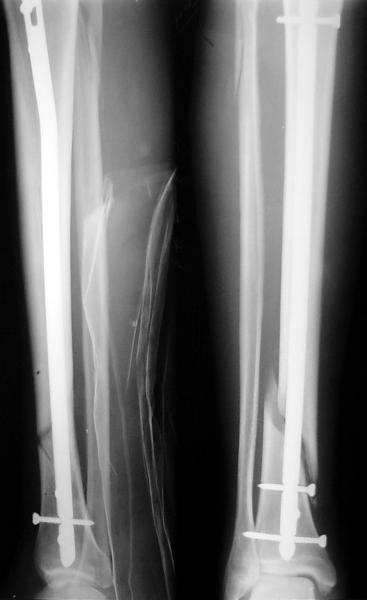

По крайней мере ходящих без дополнительной опоры через 1 месяц после операции с небольшой - при изолированной травме немало. Нестабильные по оси, кстати, не только оскольчатые, но и спиральные.

И если пациент еще не возвращается к полной нагрузке и функции, то не потому, что не разрешает врач, опасаясь несостоятельности фиксации.

Как мне показать пример? Фото стоящего на одной оперированной конечности пациента? O! Пример, подвигнувший нас на некоторое изменение технологий. Пациент этот ходил с полной нагрузкой вопреки рекомендациям. В качестве подтверждения - сломанный проксимальный статический винт к 1 мес., а к 2 мес. - все остальные. Сейчас мы перешли на более fool-proof остесинтез.

Это наглядная демонстрация возможности ранней полной нагрузки при нестабильном по оси повреждении, причем не в самых благоприятных механических условиях - при плохом сопоставлении, со слабым фиксатором.

JOM> Ваш больной имеет счастье, что первым согнулся проксимальный

JOM> замыкающий винт, а не дистальный и гвоздь не пенетрировал

Это не счастье, а тонкий инженерный расчет ;-))

Сверху - один статический винт, а снизу - три. Что раньше сломается? Конечно, он потом и нижние сломал, и Вы правы, если бы верхний динамичесий винт уже уперся бы в нижний край отверстия, будь гвоздь подлинее, перфорировал бы сустав как пить дать.

Как я уже говорил, мы сделали выводы из этого и других подобных случаев. Очевидно, решений проблемы два - либо уменьшить нагрузку, либо увеличить прочность фиксатора. Первое решение работает не со всеми больными, так что пошли по второму пути - мы больше не используем гвозди с запирающими винтами диаметром 4 мм.